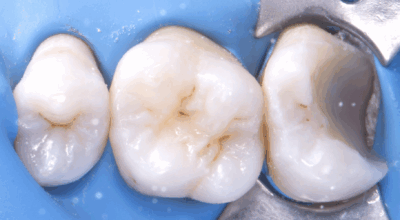

Clinical case

Direct pulp capping: 90.4% success rate